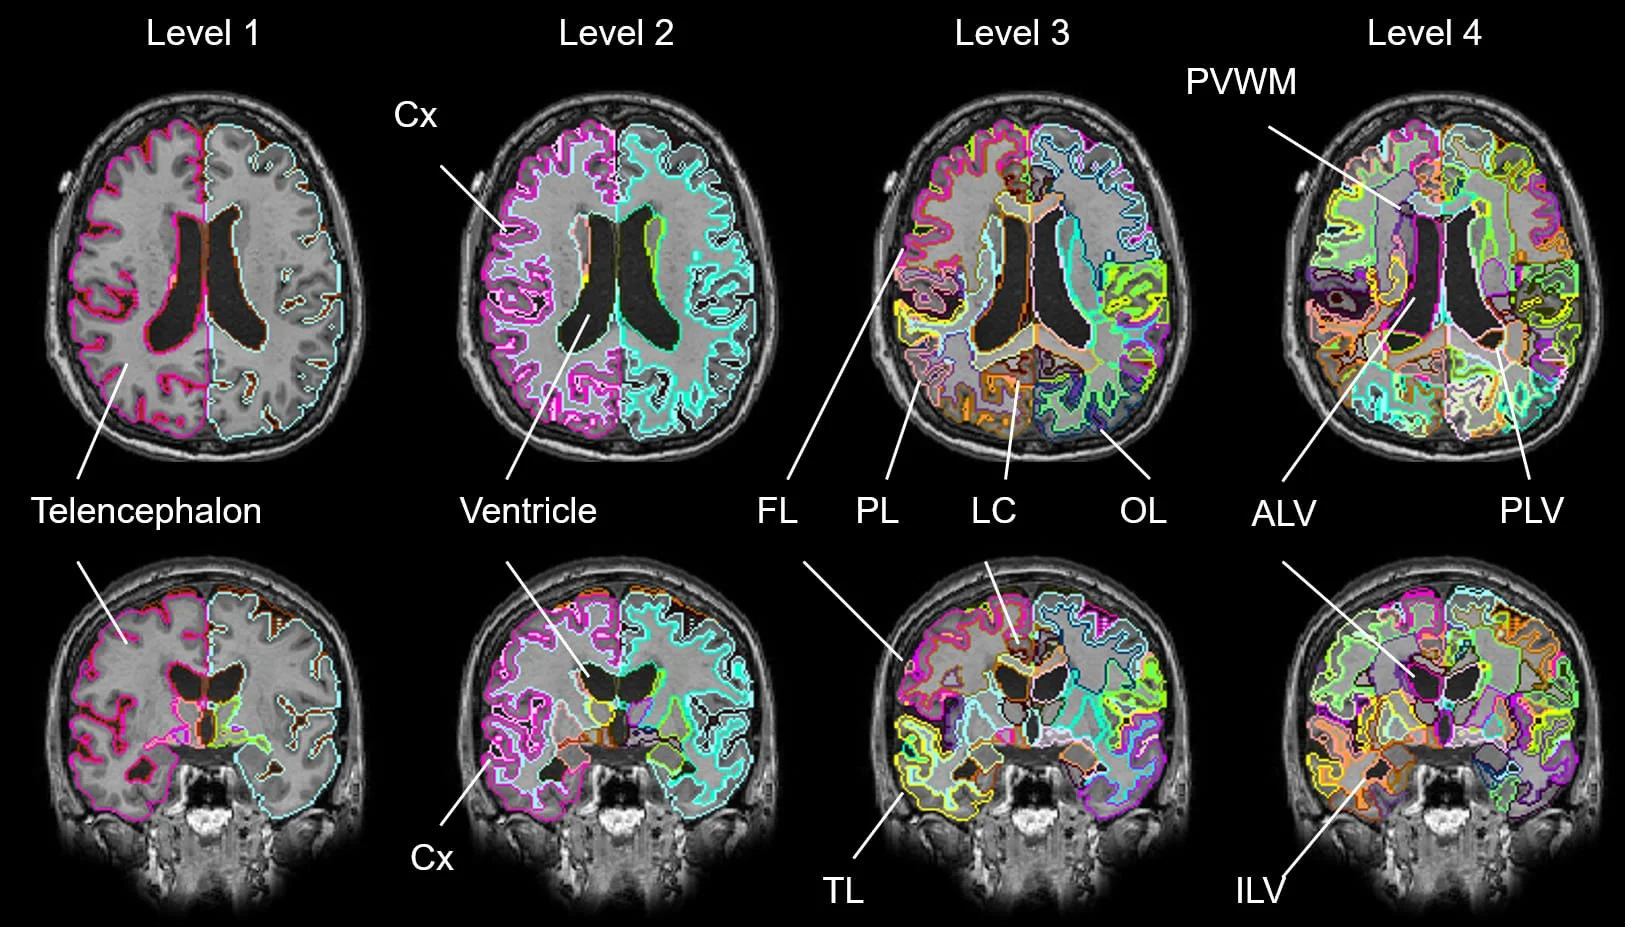

Based on AI technology, invented by Susumu Mori, the founder of Corporate M and tenured professor at Johns Hopkins University, the system quantifies the state and type of brain atrophy and the degree of vascular lesions widely seen in dementia.